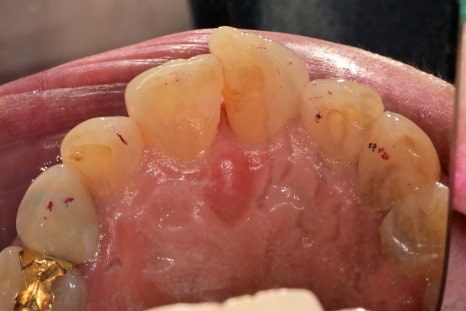

치아가 돌출되는 정도, 좌우로 회전된 정도, 치아의 겹친 부분에서

진단 모형을 제작하기 전이였지만 치아를 고르게 하기 위해서는

치아 삭제량이 상당히 많이 필요해 보였습니다.

치아의 최소삭제를 위해서 라미네이트 치료도 고민을 했었지만

진단 결과 심미적 측면에서는 크라운치료가 더 추천되는 상황이었습니다.